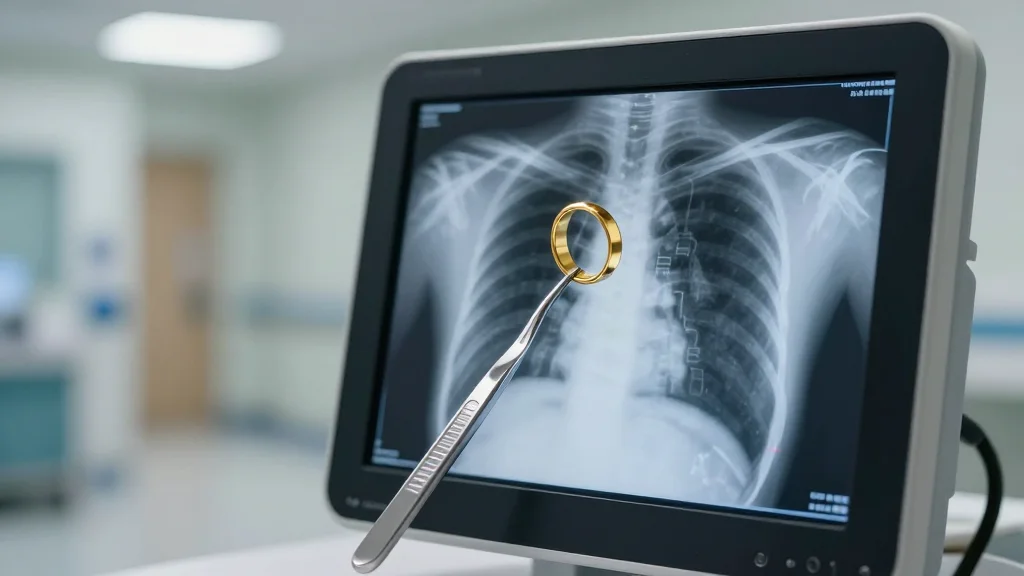

The medical imaging sector is rapidly embracing artificial intelligence to improve diagnostic speed and accuracy. Vendors that combine robust PACS infrastructure with proven AI algorithms are gaining a competitive edge, as hospitals seek to streamline workflows and meet rising demand for imaging services. Sectra, a long‑standing PACS provider, has positioned itself to capitalize on this trend by acquiring Oxipit, a company known for its autonomous chest X‑ray analysis platform ChestLink.

ChestLink’s CE Class 2B certification marks a milestone for autonomous AI in radiology, indicating that the system meets stringent European safety and performance standards. By automatically filtering out high‑confidence normal exams, the tool reduces the volume of routine studies that radiologists must review, allowing them to prioritize urgent cases. This capability not only enhances efficiency but also supports patient safety by ensuring that critical findings receive timely attention. The certification also requires continuous performance validation, underscoring Oxipit’s commitment to regulatory compliance and clinical reliability.

Swedish PACS provider Sectra completed its acquisition of AI imaging company Oxipit, adding the autonomous chest X‑ray analysis product ChestLink to its AI marketplace. The deal, first announced in March, integrates Oxipit’s team into Sectra’s Imaging IT Solutions division to expand AI capabilities.